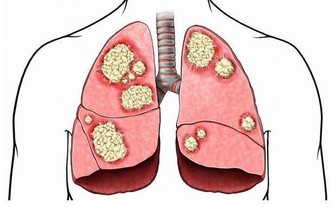

我們經常掛在嘴邊的“膝蓋”泛指下肢的膝關節,即大腿和小腿之間的連接部分,主要由骨性結構和非骨性結構組成,骨性結構包括股骨的下端、脛骨的上端、髕骨和半月板,非骨性結構包括髕韌帶、側副韌帶、交叉韌帶及其他輔助結構組成。